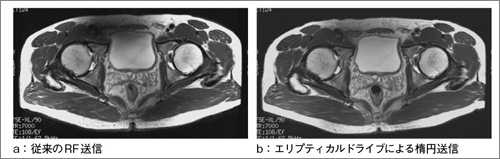

図4 エリプティカルドライブによる効果:臨床画像

従来のRF送信(a)とエリプティカルドライブによる楕円送信(b)の比較。骨盤上部における信号の低下が軽減されている。